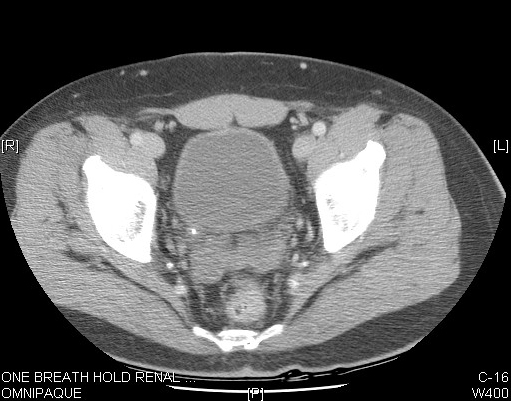

| MS1 | Image2 | Identify Ureters, Psoas in CT | What is the location and path of ureters? | Answer |